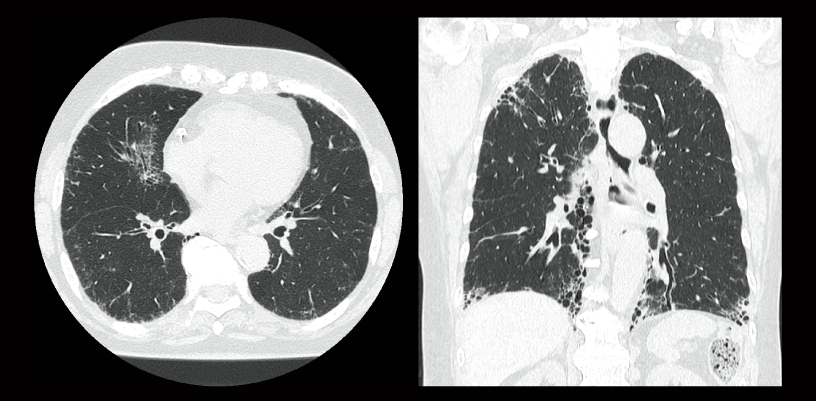

FBP(izquierda)

Intelli IPV(derecha)

Neumonía intersticial